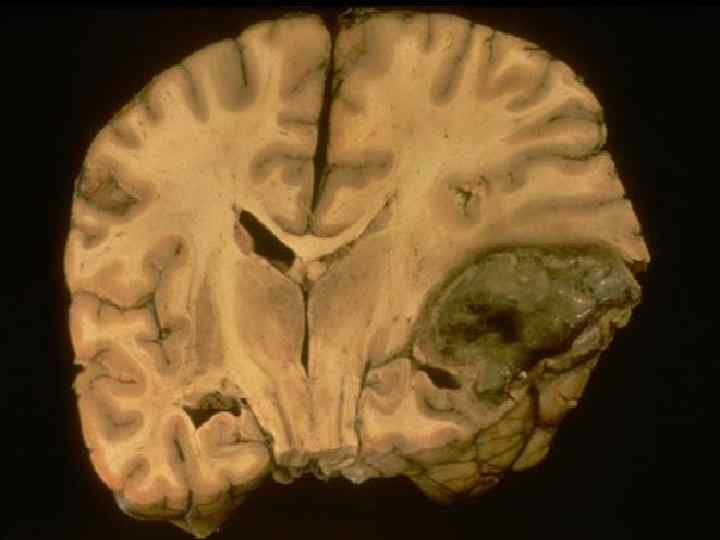

3Глюкоцереброзидоз (болезнь Гоше) Главное- дефицит глюкоцереброзидазы и накопление глюкоцереброзидов в цитоплазме клеток разных органов. Патанатомия – дистрофия печени, увеличение селезенки, распространенная дистрофия и гибель нервных клеток коры головного мозга. Геморрагический синдром- кровоизлияния в разных органах. Клиника: 1 хроническое течение 2 гепатоспленомегалия 3 гиперпигментация 4 слабоумие